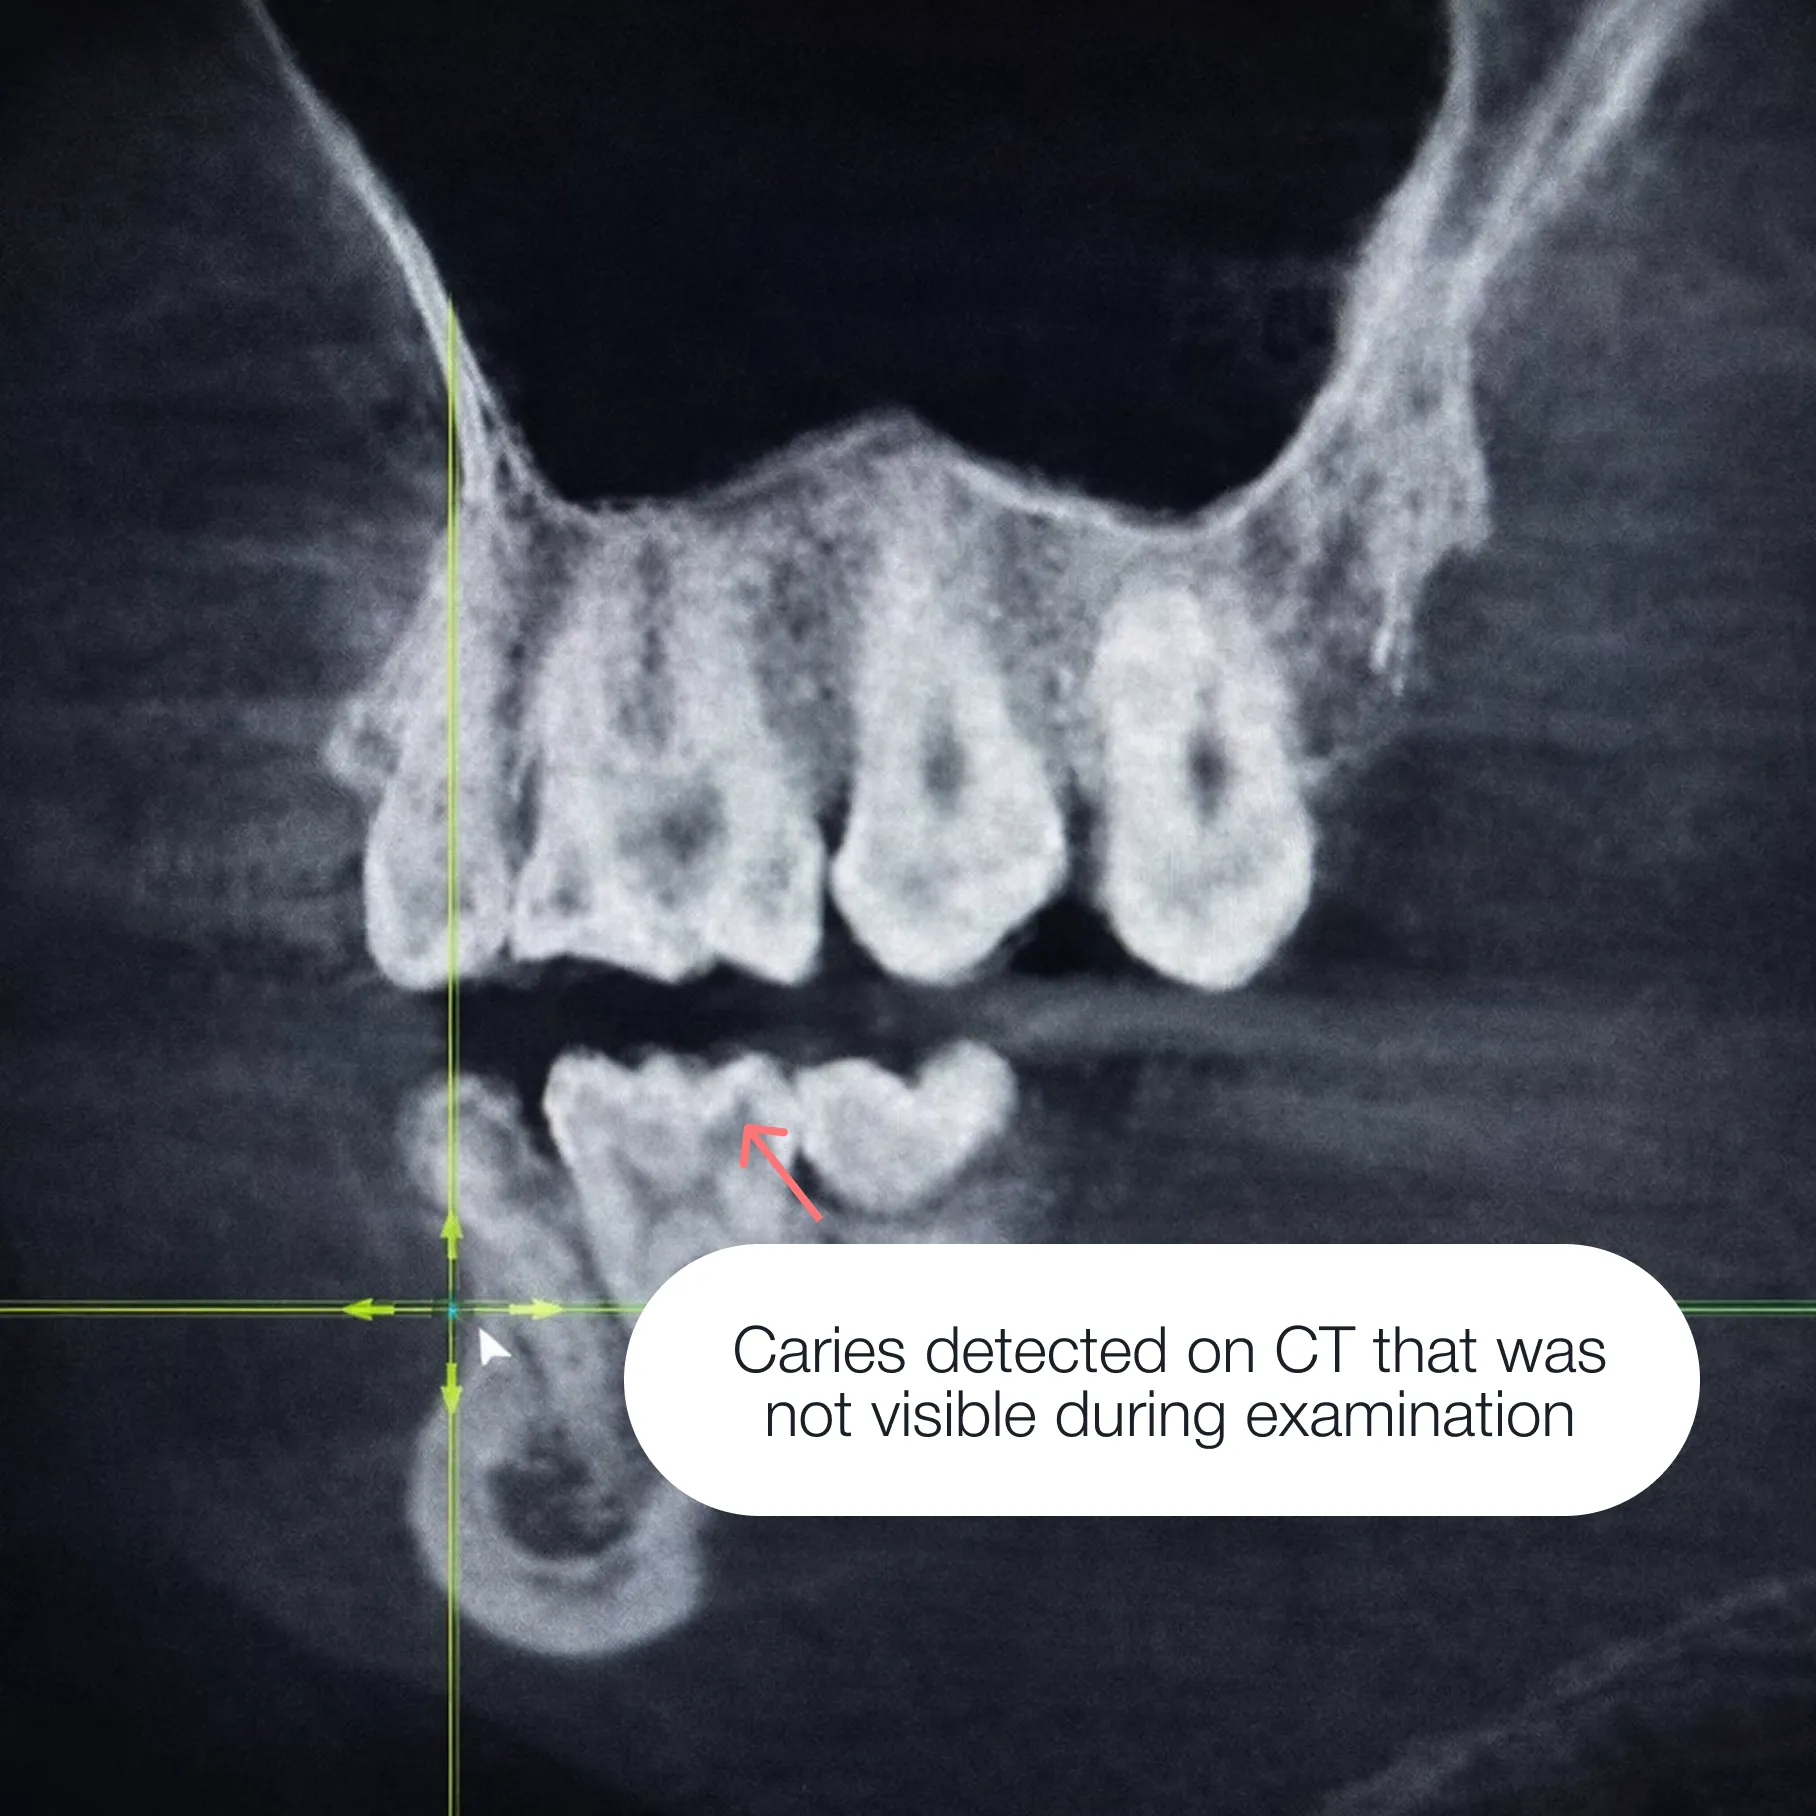

Caries spread from the inside, and if treatment is delayed, the damage will deepen. This can lead to:

Early intervention allows the tooth to be fully preserved and prevents complications.